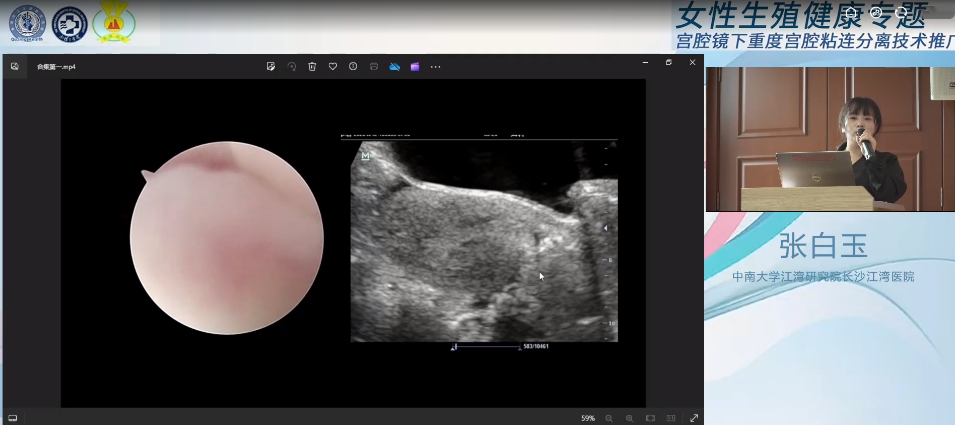

会议分为宫腔镜手术演示和主题授课两部分进行,首先由徐大宝教授搭档我院超声影像科张白玉副主任演示了多台精彩的宫腔镜手术。在张白玉3D超声技术无创、精准的术中引导下,徐大宝教授成功为两位患者顺利分离了粘连,恢复了正常宫腔形态,为患者后续生育带来了极大的希望。

在随后环节中,张白玉副主任带来《宫腔手术术中超声监护策略》的主题授课。她介绍,术中超声是指手术过程中采用超声技术辅助手术医师诊治疾病的方法,目前实时腹部超声监护已经成为妇科宫腔镜手术监护的首选方法,具有便利、可重复性好的优势,与宫腔镜手术联合,无腹部创口,创伤小、不破坏盆底结构,能减少手术并发症并提高手术成功率。通过授课,张白玉将术前精准诊断宫腔粘连、术中超声经验和诸多前沿技术倾囊相授,与会人员纷纷表示受益匪浅。